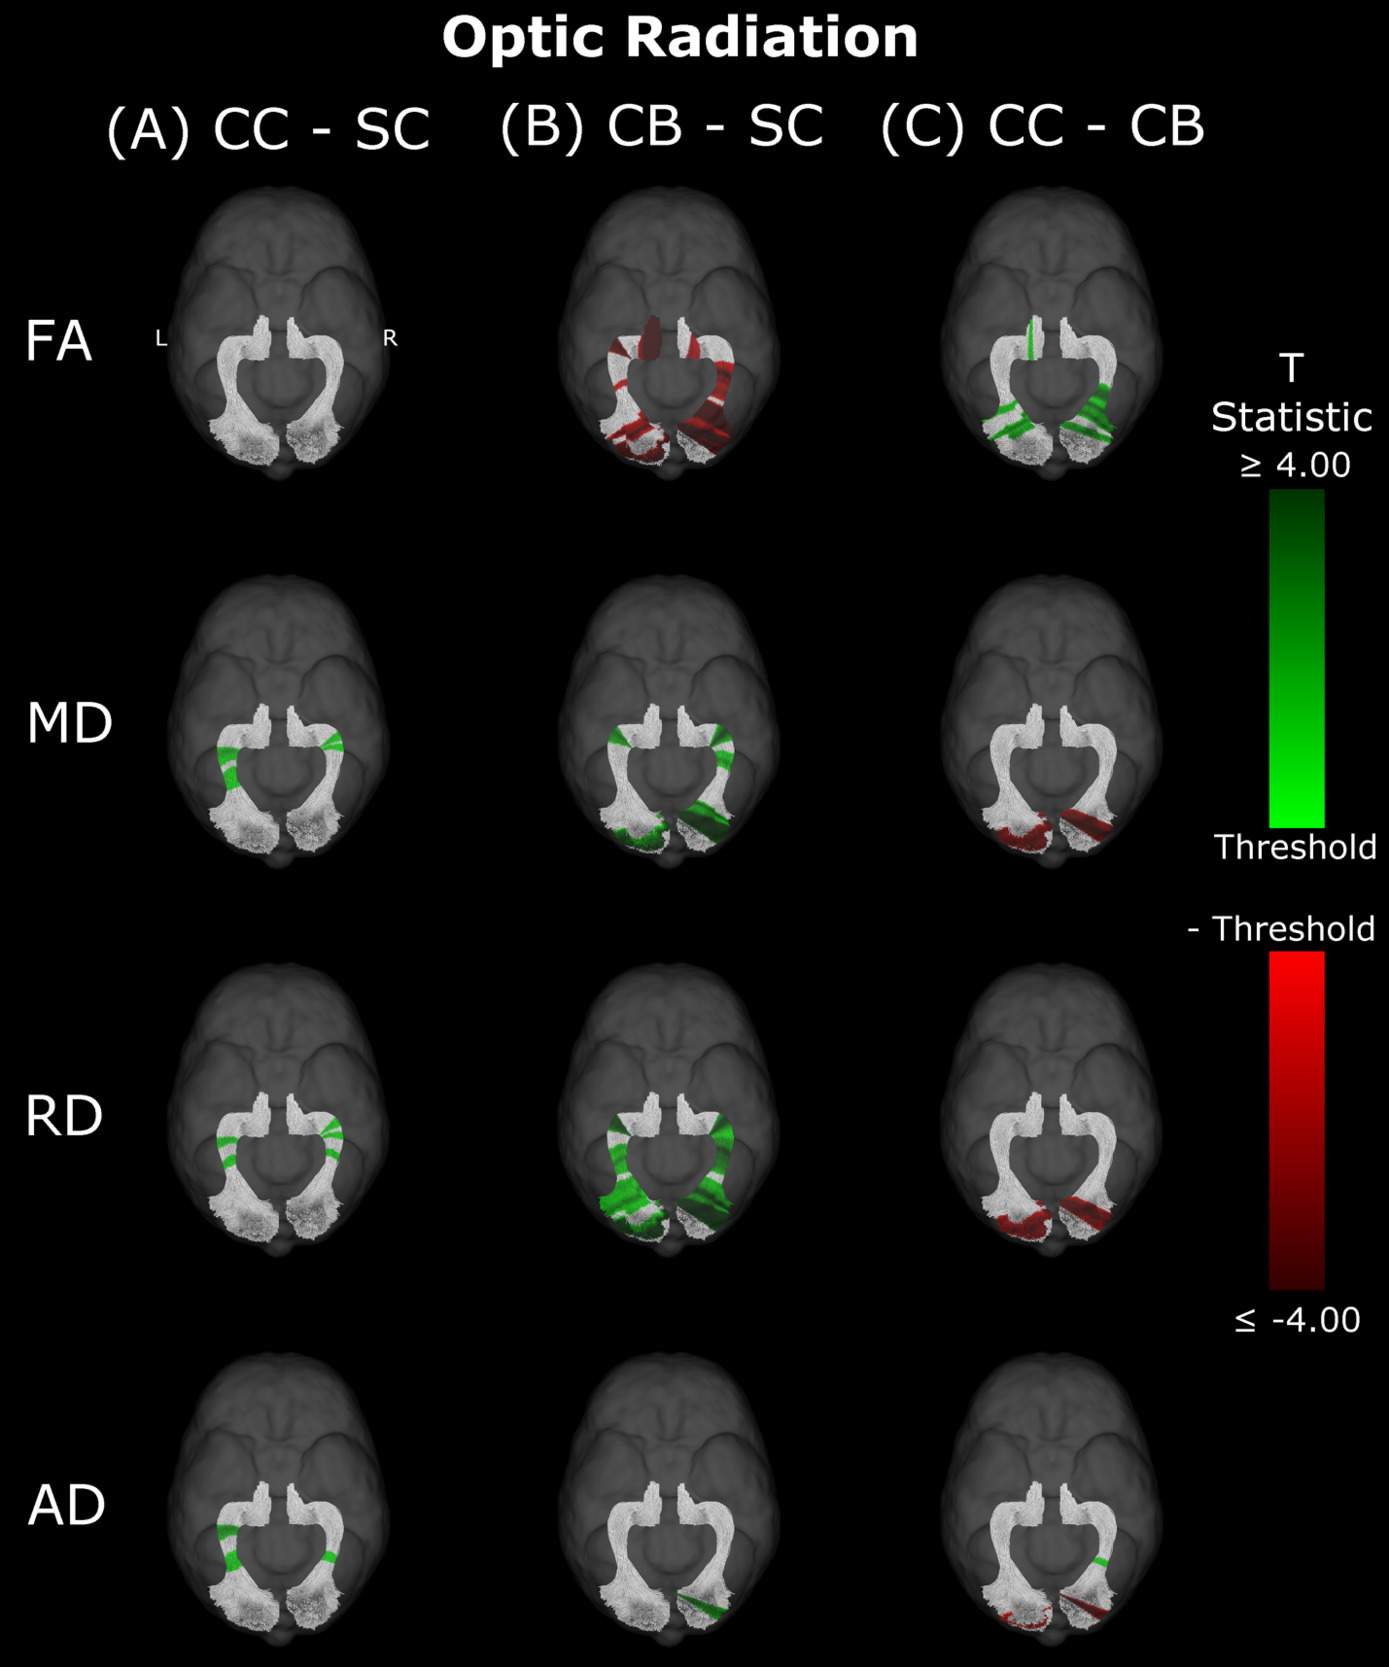

Optic Radiation

Compared to SC subjects, CB individuals exhibited significantly decreased FA and increased MD, RD and AD (Figure 2B, Table 2). While no significant difference was observed for FA, measures of diffusivity were increased in CC compared to SC individuals as well (Figure 2A, Table 2), although differences were less spatially extensive (MD and RD). Comparing CC to CB participants directly revealed that FA was higher for CC individuals, while MD, RD and AD were lower (Figure 2C, Table 2). These differences mostly existed bilaterally, and many clusters appeared to show some degree of spatial overlap across hemispheres. Furthermore, some level of spatial similarity was visible across comparisons, such that some significant CC vs SC clusters for MD and RD were significant for CB vs SC too. Additional CB vs SC clusters showed spatial overlap with CC vs CB clusters, in regions where no significant differences were observed for the CC vs SC comparison (mostly near the occipital terminals of the tract). In contrast, there was very little apparent overlap between CC vs SC and CC vs CB comparisons.